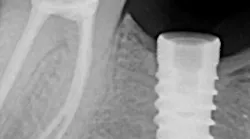

There are many different types of screw/implant retrieval and rescue kits made by different companies. Nobel Biocare, Neobiotech, Osstem (OssVK), BTI Biotechnology Institute, and Salvin Dental Specialties all make these types of kits. The author has found great success with screw retrieval using the Implant Rescue Kit from Salvin Dental (figure 3). This kit is especially useful when the broken screw is fractured in the apical 50% of the implant chamber (figure 4). Following are the steps involved in using this implant screw retrieval kit (figure 5).